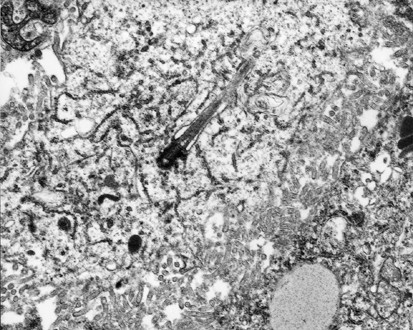

The most common ultrastructural characteristics of the mesotheliomas were the presence of long, slender, often branching, undulating microvilli on the apical surface of the cuboidal cells lining the tubules or papillae (Figure 3a, b), dilated intercellular spaces (Figures 3a and 4), and intracellular lumens (Figures 5 and 6). On occasion, a profusion of microvilli was also seen on the basal surface of the cells (Figure 7a) or involving the entire cell membrane (Figure 7b). The cytoplasm usually exhibited large amounts of intermediate filaments often arranged in bundles (Figure 8). A variable amount of glycogen was also a common finding (Figure 6). A rare cell exhibiting a single cilium was identified in three of the cases, and, in one of these, the cilium was intracytoplasmic (Figure 9).

In the serous carcinomas, microvilli were present only on the luminal or papillary surfaces. They were usually straight, varied in length, and were fewer in number than in the mesotheliomas (Figures 10a and 11). The cell membranes were closely apposed and sometimes appeared to be interdigitating, especially in the low-grade tumors (Figure 12). Multiciliated cells were occasionally seen in some of the low-grade serous tumors, and a large number of microvilli were distributed between the cilia on the surface of these cells (Figure 10a, b). A few or a single cilium were often found in the higher-grade serous carcinomas, but, in general, these structures tended to be less common in the less-differentiated tumors (Figure 13). Small bundles of intermediate filaments were only rarely identified in the cytoplasm of three cases.

In all of the cases in which electron microscopy studies were performed, this technique allowed the differential diagnosis to be clearly established between epithelioid mesothelioma and serous carcinoma. The mesotheliomas were characterized by a profusion of long, slender, wavy microvilli occurring along any of the surfaces of the cells. This is in contrast to the serous carcinomas in which the microvilli were less numerous, and straight, and, although they were of varying lengths, they were in general shorter and confined to the luminal and papillary surfaces. Additionally, the cell membranes in the serous carcinomas were intimately apposed, while, in the mesotheliomas, intercellular gaps that often exhibited microvilli were a common finding. Similar to previous ultrastructural studies, large collections of intermediate filaments arranged in tonofibrillar bundles and intracytoplasmic lumens covered by microvilli were common findings in mesotheliomas,65, 66, 67 but not in serous carcinomas.68, 69, 70 No intracytoplasmic lumens were identified in any of the serous carcinomas investigated, and only rare small bundles of intermediate filaments were found in a few cases. Another finding that was helpful in distinguishing serous carcinomas from mesotheliomas was the presence of multiciliated cells in serous carcinomas, but not in mesotheliomas. Multiciliated cells, such as those shown in Figure 10a and b, have previously been reported in serous carcinomas and are more often found in low-grade serous carcinomas and serous tumors of borderline malignancy originating in the ovary and peritoneum.23, 24, 69, 70, 71, 72 Neither in the present study nor in previous investigations have these cells been found in mesotheliomas. Cells presenting a solitary cilium or a few cilia have frequently been found in serous carcinomas, including those of high-grade malignancy; however, their occurrence in mesotheliomas is exceedingly rare.73, 74